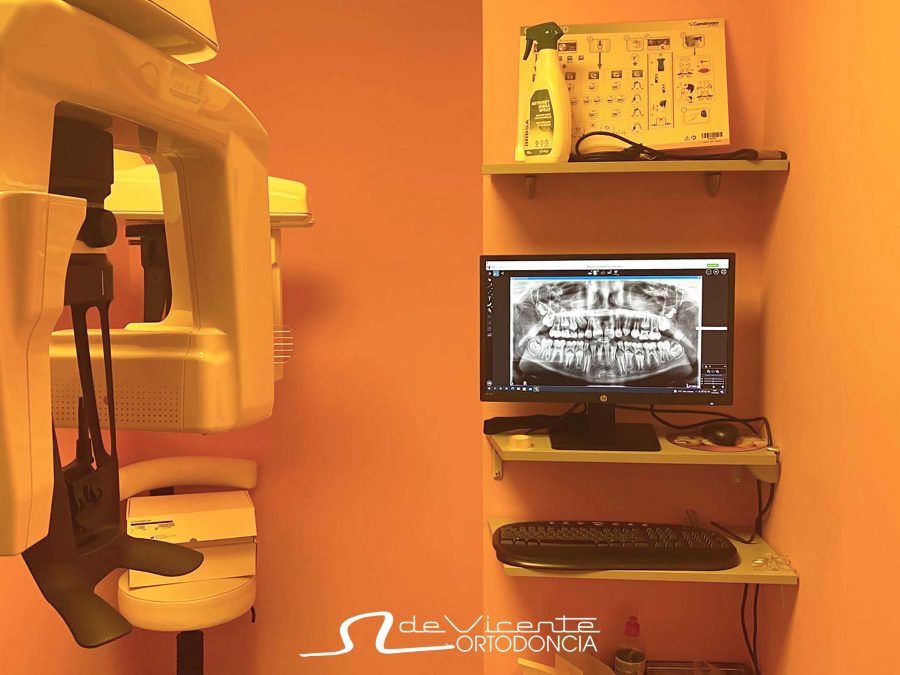

El nuevo aparato del que disponemos en la clínica dental De Vicente Ortodoncia es un CBCT o también llamado tomografía computarizada de haz cónico. Se parece a un TAC convencional y nos permite ver en 3 dimensiones los tejidos duros del paciente, es decir, principalmente el hueso y los dientes. Es similar a una radiografía pero en 3D. Sin embargo, utiliza menos radiación, con unos resultados a nivel de definición y calidad muy altos.

En la clínica dental De Vicente Ortodoncia priorizamos la calidad de nuestro servicio a nuestros pacientes. Por eso, disponer de una prueba diagnóstica potente que aporta tanta información como la que ofrece este escáner 3D o radiografía 3D en nuestra propia clínica, es sinónimo de calidad asistencial. Además, con este solución tecnológica también reducimos el tiempo de espera y podemos garantizar que ofrecemos un tratamiento eficaz y seguro.

Se puede realizar a cualquier paciente que necesite una radiografía 3D / CBCT / TAC intraoral, aunque sea para otra clínica. La información les será entregada en un CD o enviada por correo electrónico. Además, la maquinaria es último modelo, con lo que la calidad es altísima y servirá sin duda para aquel que lo necesite.